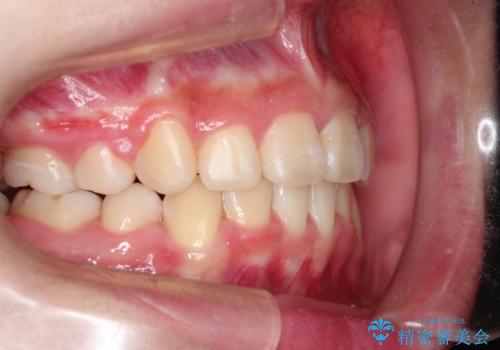

抜歯矯正で口元に変化を ラビアル・ワイヤー矯正でEライン

- 上下左右4本の小臼歯を抜歯、ラビアル・ワイヤー矯正を計画した。

抜歯をして第1小臼歯分のスペースを獲得することにより、ガタつきの改善と前歯のリトラクトをおこない、横顔の印象もすっきりとし、整ったEラインを作ることができました。